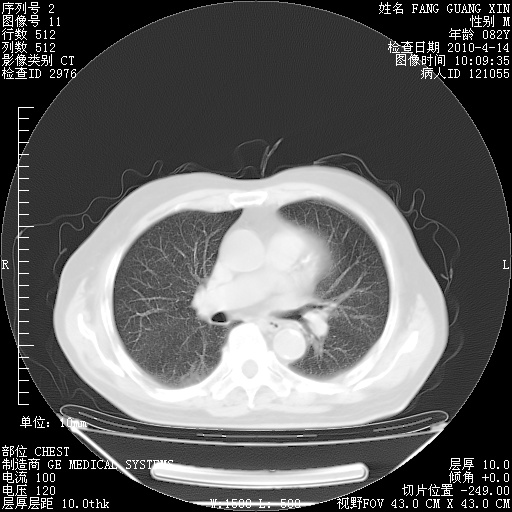

4月14日肺部CT